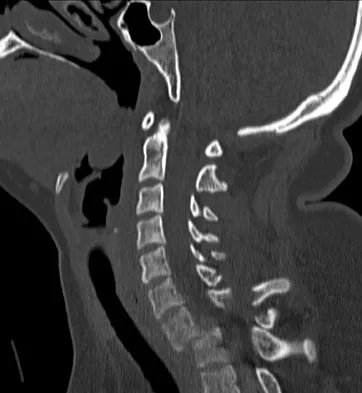

Figures 3a and 3b show the MRI scans of a patient with neck pain. What is the most likely diagnosis?

Muliple neurofibromas result in marked foraminal enlargement as seen on the sagittal MRI scan. Collagen disorders leading to dural ectasia may show similar enlargement, but none of these is listed as a possible answer. Kim HW, Weinstein SL: Spine update: The management of scoliosis in neurofibromatosis. Spine 1997;22:2770-2776.